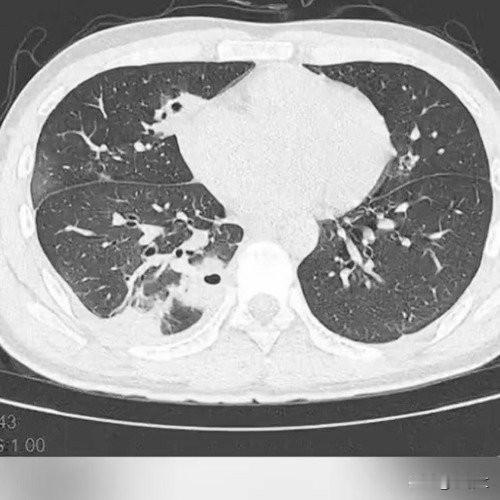

挤一颗痘痘竟致肺里现十几个空洞!大二学生的惨痛教训 20岁的大二学生小林为备考熬夜后,脸部冒出一颗黄豆大小的红肿痘痘。因觉得影响美观,他未洗手便对着镜子将其挤掉,当时看着脓水流出还倍感清爽。 然而几天后,痘痘不仅持续化脓,小林还出现发烧、咳嗽、咳痰等症状,退烧药仅能暂时缓解不适,右下胸更是传来针刺般的疼痛,深呼吸、咳嗽时疼得直冒冷汗。熬至第三天,体温升至39℃的小林紧急前往宁波大学附属第一医院就诊。 接诊的丁群力主任医师通过CT检查发现,小林肺内出现十几个空洞,部分肺组织已坏死,确诊为血源性肺脓肿。细菌培养和基因检测显示,其血液中检出的金黄色葡萄球菌是“元凶”——该细菌原本存在于皮肤表面,而小林挤的痘痘位于脸部“危险三角区”,未洗手的操作让细菌在挤压压力下进入血管引发败血症,进而随血流侵入肺部,侵蚀肺组织导致严重感染。医生提醒,脸部危险三角区的痘痘切勿随意挤压,皮肤出现感染需及时科学处理,避免引发致命风险。